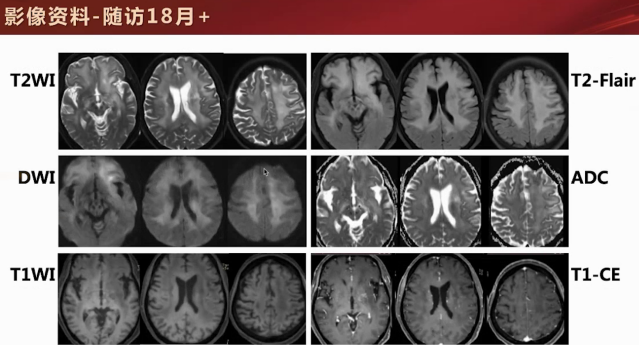

18个月后:经规律治疗,病灶实性区域缩小,出现局部囊变,强化区域呈点状,水肿范围扩大。激素治疗后FDG - PET代谢显像,病灶区域代谢未见明显升高。